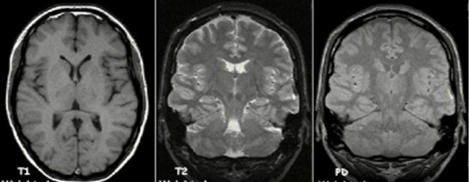

Patients is placed inside the strong magnet at still position to reduce motion artefacts in the image. MRI produced detailed anatomical structure of the brain,20 spinal cord and other body parts, it has the advantage of being able to visualized anatomical images in three planes: axial, sagittal and coronal views.21 MRI has the advantages of giving higher soft tissue contrast and being able to detect blood flows and cryptic vascular malfunctions, MRI has the advantage of being free from ionizing radiation exposure over computed tomography (CT) and conventional x-ray machines. T1-weighted, T2-weighted, diffusion weighted imaging (DWI), Proton density (PD-weighted), Fluid attenuated inversion recovery (FLAIR), Auto-calibrating reconstruction for cartesian imaging (ARC), and Generalized Auto-calibrating partial parallel acquisition (GRAPPA) are the imaging sequences used in magnetic resonance imaging (MRI). ARC is multi-coil parallel imaging (PI). Based on the time to echo (TE) and repetition time (TR), T1-weighted and T2-weighted are generated. T1-weighted has longer TE and TR. Another difference is by looking at cerebrospinal fluid (CSF), CSF is darker in T1-weighted and bright in T2-weighted images. The FLAIR sequence is mainly T2-weighted image with longer TE and TR. Diffusion weighted image is used to detect random movement of water proton. Proton density is in between T1 and T2 with pulse sequence of long TR and short TE.21 MRI is broadly classified into structural magnetic resonance imaging (sMRI) and functional magnetic resonance imaging (fMRI), sMRI is mostly applicable to clinical practices and research purposes. The distinction between sMRI and fMRI is difficult to make as function and structure are closely related, from biological view point fMRI provides dynamic physiological information which includes blood oxygen level depended (BOLD), perfusion and blood flow, while, sMRI displays static anatomical information which include studies of epilepsy, schizophrenia, dementia, trauma, tumours and multiple sclerosis.22 Structural MRI sequence has high contrast between gray matter and white matter giving room for volume quantification of the gray and white matter.  The common method used for processing sMRI is voxel-based morphometry, it can also be used to assess the degree of cortical folding or pattern and variation of cortical gyrification. sMRI has the advantages of clear interpretation, early implemented across centres and relatively low cost over fMRI, electroencephalography and proton magnetic resonance spectroscopy23 (Figure 8).

Figure 8 Example of T1 weighted, T2 weighted and PD weighted MRI Scan.